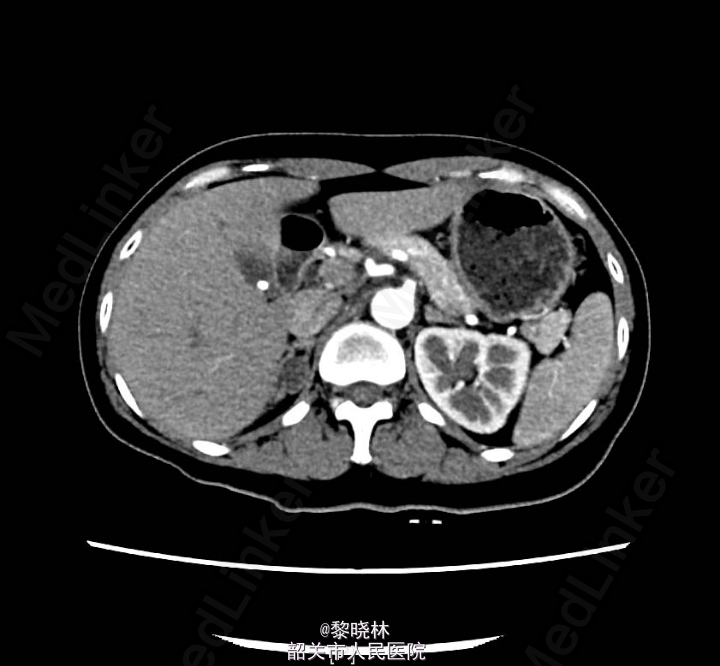

入院查体:BP182/111mmHg,余无特殊。辅助检查门诊CT示双肾+肾上腺螺旋CT平扫+增强扫描(中腹)检查所见:1、右肾上腺结节,考虑腺瘤;左肾上腺增生。2、左肾下盏结石。3、小副脾。

诊断:高血压查因:肾上腺瘤?

入院后查尿蛋白定量/尿肌酐比值 尿总蛋白0.030g/L,尿肌酐4019.000umol/L。高血压三项 醛固酮547.930pg/ml,肾素浓度23.520pg/ml,血管紧张素II137.070pg/ml。 血清钾、钠、氯测定 钾2.930mmol/L。血常规、尿常规、大便常规、生化、甲功、肿瘤标志物、胸片、心电图均未见明显异常。排除手术禁忌症后,于2015-03-16行右侧后腹腔镜下肾上腺肿物切除术,术后病理提示“右侧肾上腺皮质腺瘤”。